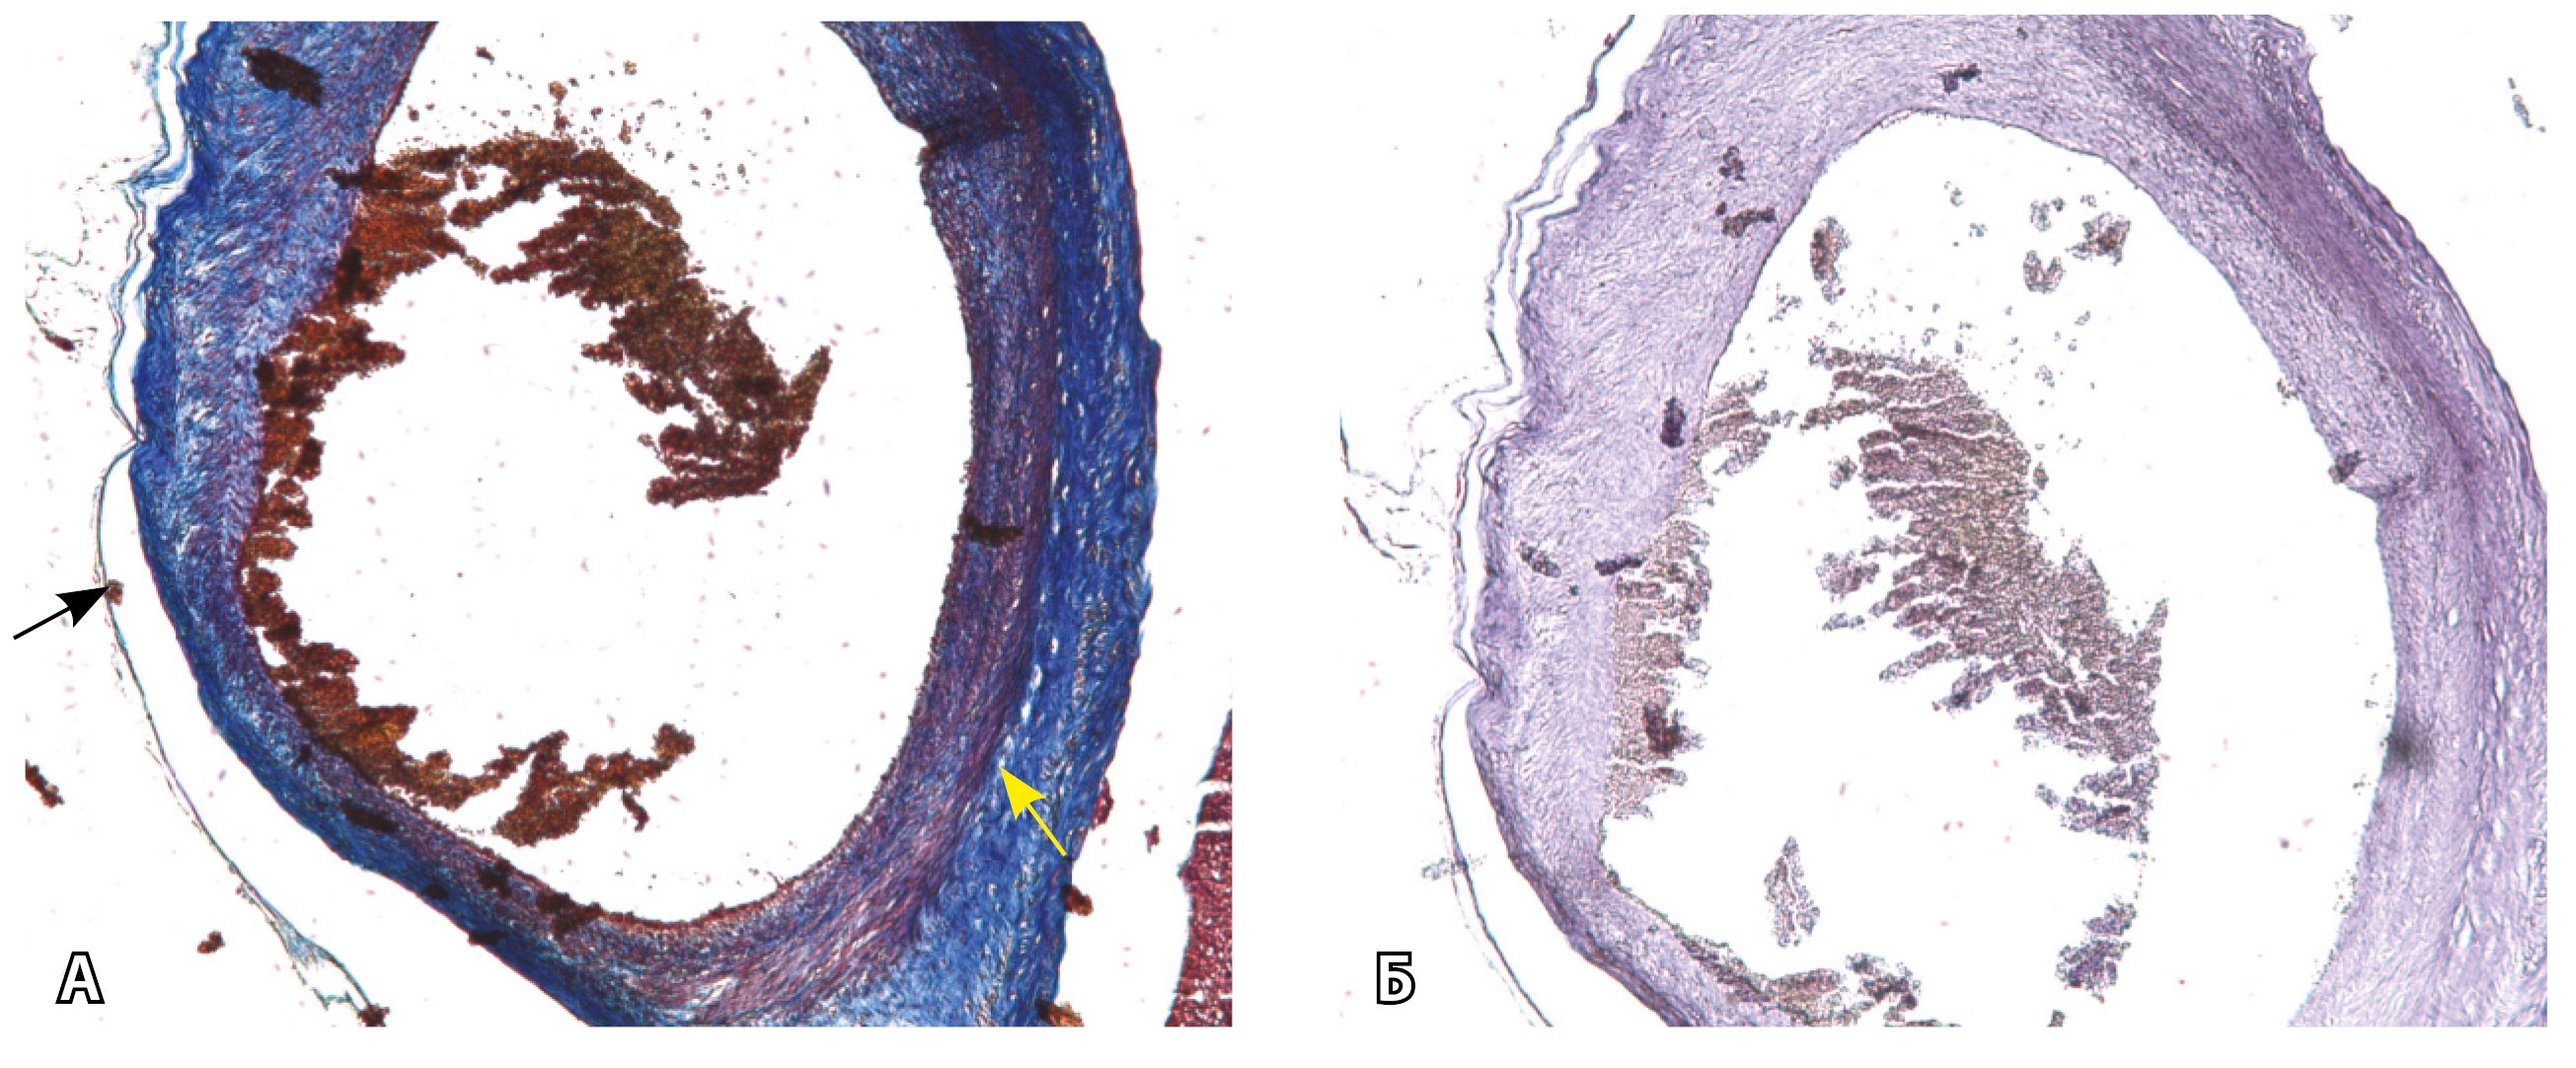

Эластический каркас представлен сетью тонких волокон, без концентрации на внутреннюю и внешнюю мембраны. Однако маркер СD34 констатирует сохранение эндотелия, что свидетельствует о том, что по артериям циркулирует кровь, не сворачиваясь (рис. 13).

Рис. 13. Самые крупные сосуды в пределах серозной оболочки стенки матки: А, Б – серийные срезы артерии; × 50. При окраске по Маллори (А) видна тонкая полоска мезотелия (черная стрелка), слабо дифференцированная мышечная стенка артерии, вокруг нее – плотная коллагеновая оболочка (желтая стрелка), в просвете определяются тромботические массы. При окраске по Вейгерту (Б) наблюдается полная потеря внутренней и внешней эластических мембран